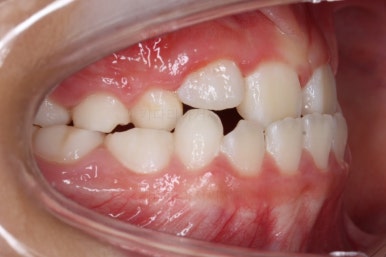

우선 처음 내원 하셨을 때의 입안의 상태를 보겠습니다.

아직 나이가 어리다 보니 곳곳에 유치가 남아 있었어요. 보통 이렇게 영구치가 다 나오지 않았을 경우, 보호자분들은 "치아교정"에 대해서는 전혀 생각해 보시지 않으셨을 수 있어요.

이번 환자분의 경우도 앞니가 거꾸로 물리는 상황이어서 치료가 필요한 상황이였습니다.